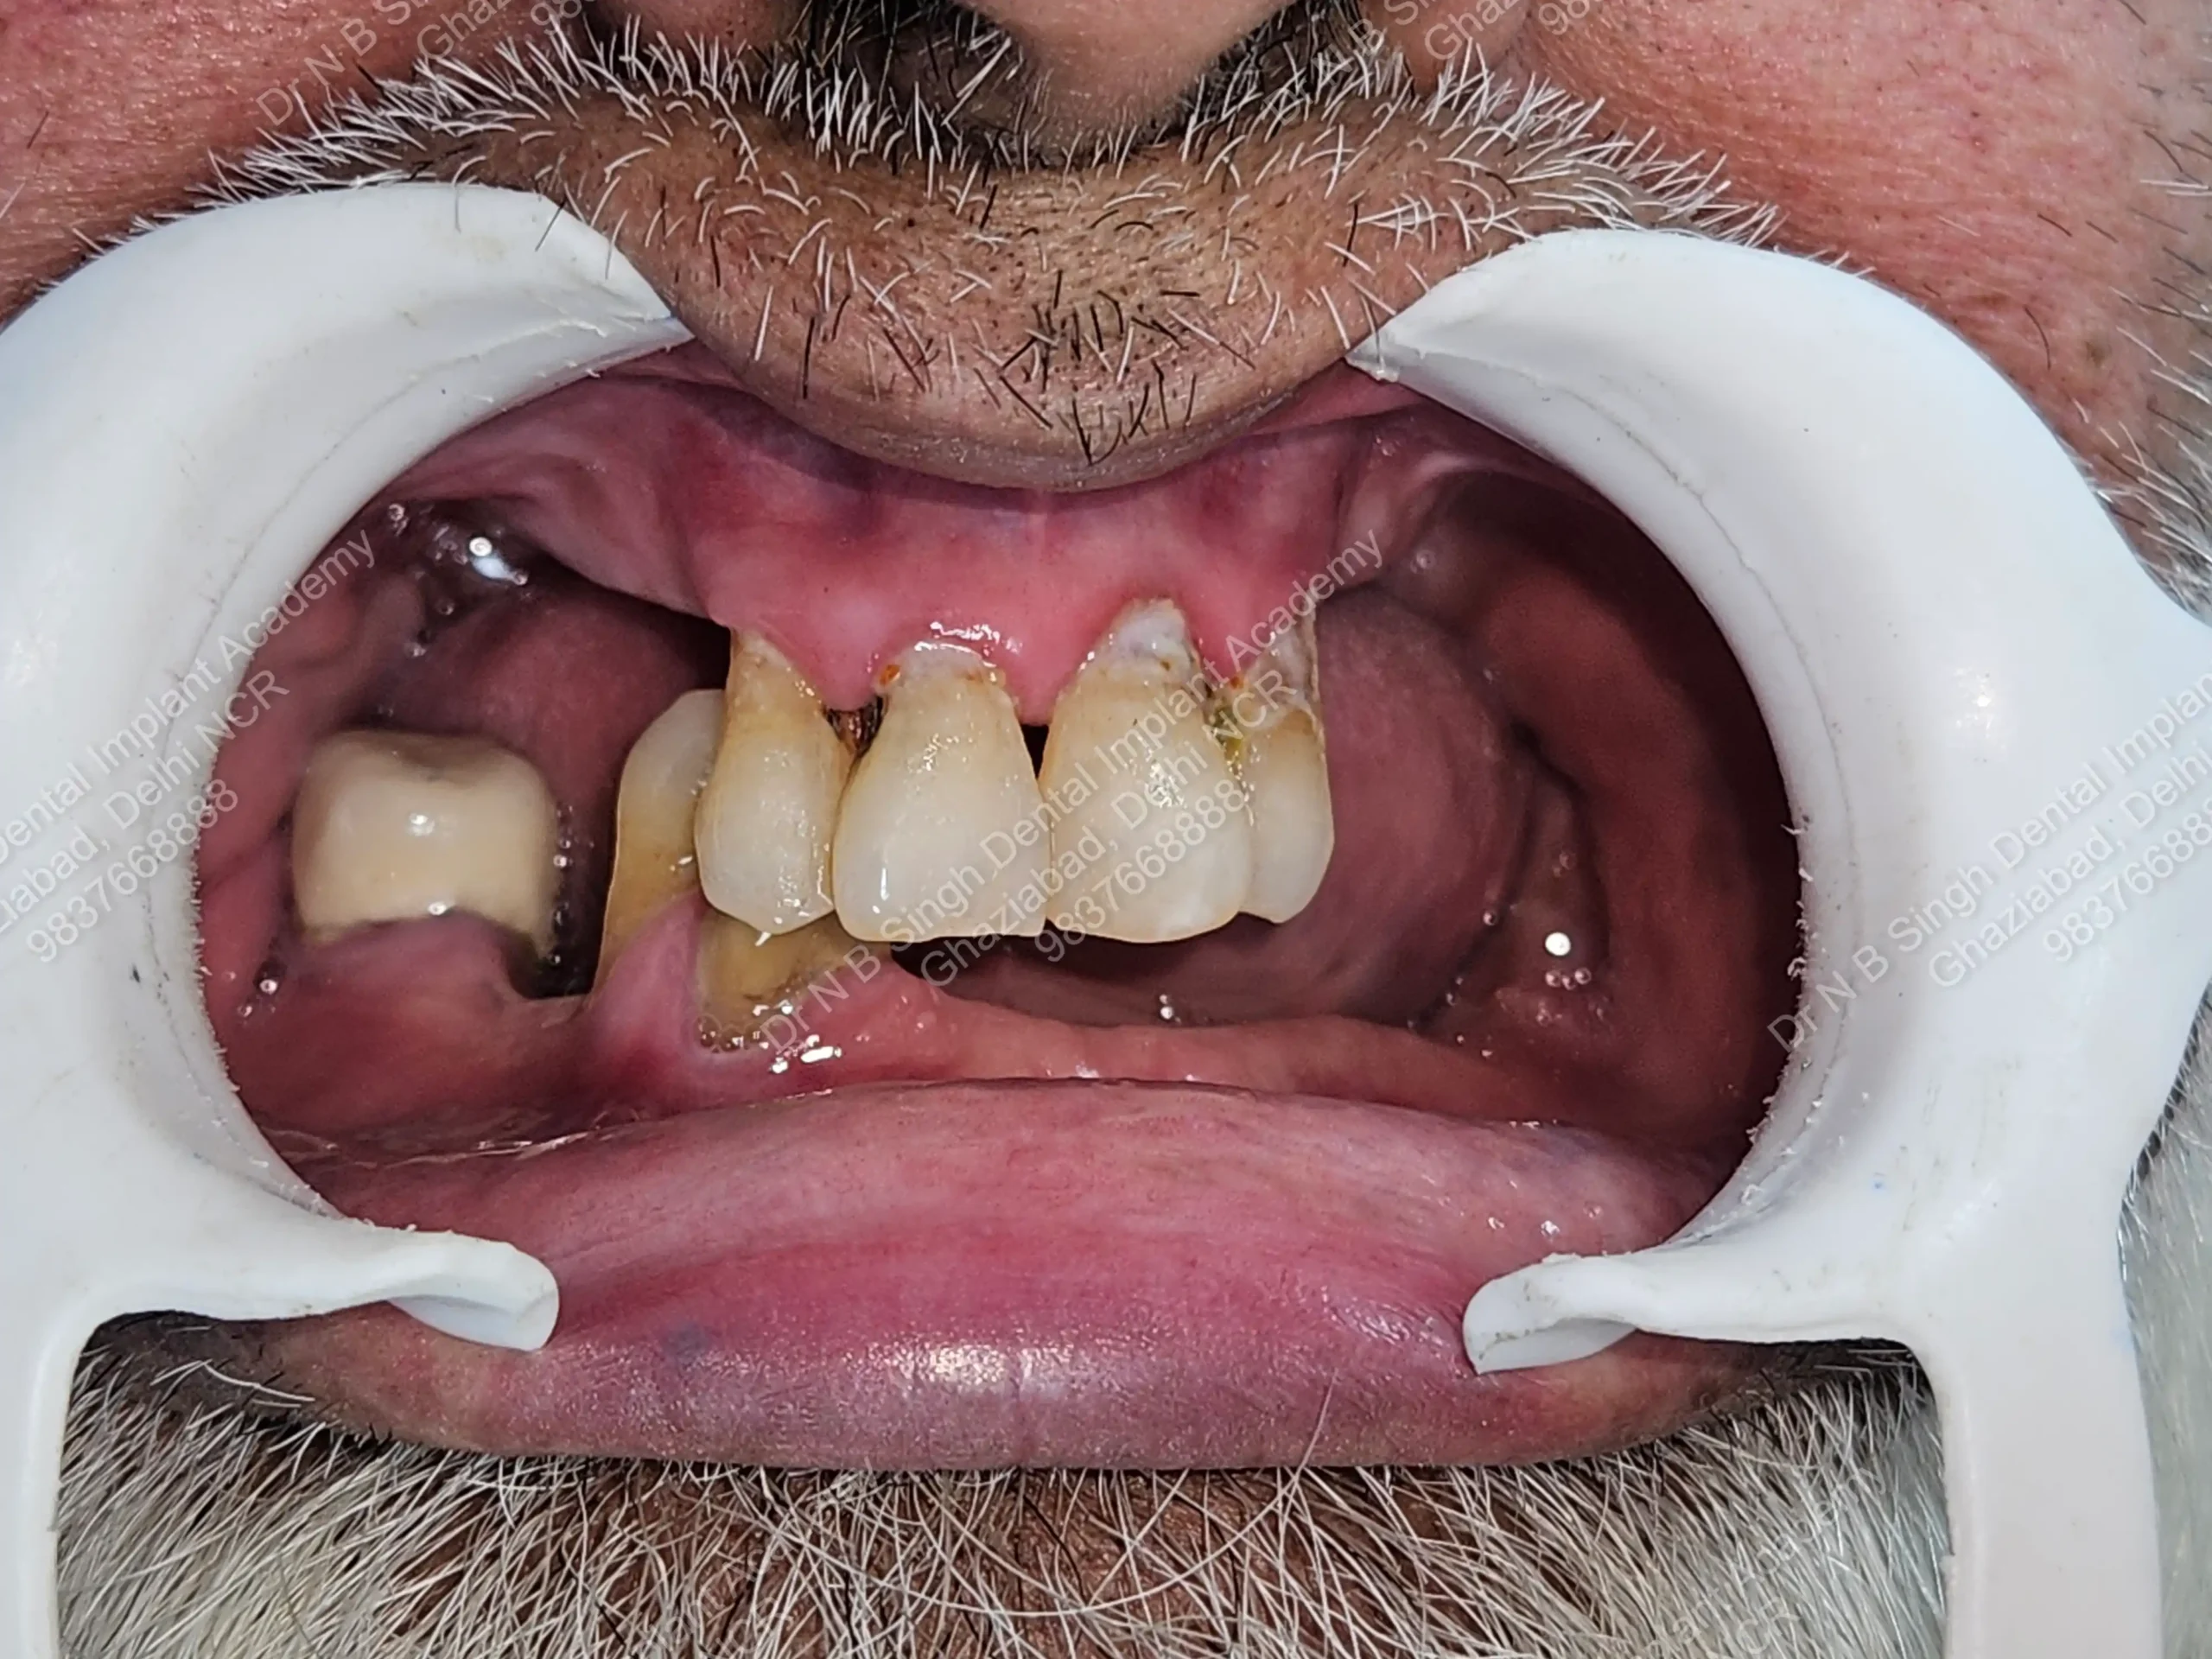

A008 Basal implants – af-qurs 1

Dr. N.B. Singh